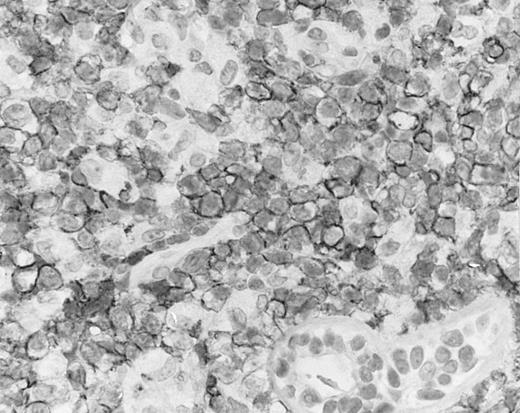

Lymph node biopsy of aggressive NK cell leukemia/lymphoma (case no. 37). There is a fairly monotonous, diffuse infiltrate of medium-sized cells with round nuclei. The neoplastic cells in this case resemble plasmacytoid monocytes.